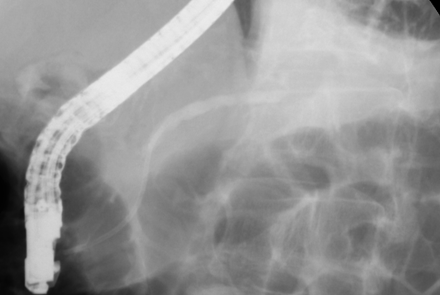

둘째는 삽관된 카테터로 방사선 조영제를 주입하여 담관 또는 췌관에 대해 방사선 투시 및 촬영을 하여 진단을 하고 필요하면 유두부를 절개하여 담관-췌관의 병을 치료하는 것이다. 이런 시술을 내시경 역행성 담도-췌관 조영술(ERCP)이라고 한다. 즉, 이 검사는 내시경 검사와 방사선 검사 둘 다를 포함한다. 따라서 ERCP를 시술하는 의사는 내시경 술기와 투시 조영술 모두에 전문가이어야 한다. 또한 ERCP를 이용한 중재적 시술은 상부소화관내시경 검사보다 시간이 더 걸리고 중증의 합병증 위험이 있어서 모든 내시경의사가 ERCP를 할 수는 없고 전문적인 수련 과정을 이수한 후에 시술을 하는 것이 바람직하다.

ㆍ담관 결석의 제거

ㆍ담관염의 치료를 위한 담즙액의 배액

ㆍ담관암이나 췌장암, 전이암에 의한 담관폐쇄의 치료